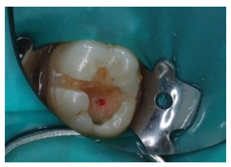

3.4. Clinical Scenario #4

With regards to this clinical scenario, the majority of surveyed students (92.7%) selected, as a first treatment option, “direct pulp capping”. Among those who selected “direct pulp capping”, 68.4% would then place a “temporary restoration”, and 31.6% a “definitive restoration”. Additionally, 2.4% would perform a “root canal treatment” and then place a “definitive restoration”, 4.9% would carry out a “root canal treatment” and then place a “definitive restoration and a crown”. The alternative “direct pulp capping and definitive restoration” was considered as correct (Figure 1).

Upon carious lesions with a greater extension, the therapeutic approach becomes varied depending on the extent of the lesion. When the pulp is reversibly affected, or an accidental pulp exposure is produced when removing affected tissue from deep carious lesions, the preservation of pulp vitality is preferable [31,37]. A direct pulp capping is indicated in cases where an asymptomatic pulp exposure with a controllable bleeding is produced, and the tooth is restorable. Pulpotomy is reserved for pulp exposures of greater size (>1 mm) and whose bleeding can be controlled within a period of 1–2 min [21]. The results from our study show that the surveyed students majorly coincide with the current recommendations for the treatment of the vital pulp. The participants would perform a pulp capping on clinical scenarios 2 and 4. However, the majority of them would then place a temporary restoration (i.e., two-stage selective caries removal), while available evidence supports one-stage selective removal procedure [20,38].